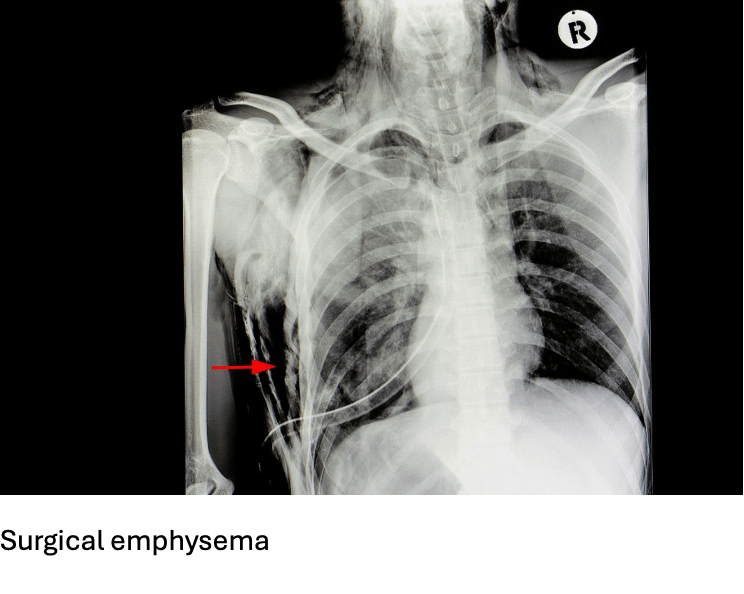

Answer: A) Air leakage into subcutaneous tissue

Explanation: Surgical emphysema (or subcutaneous emphysema) occurs when air leaks into the subcutaneous tissue, usually from chest trauma or pneumothorax. It causes crepitus (crackling sensation) under the skin.